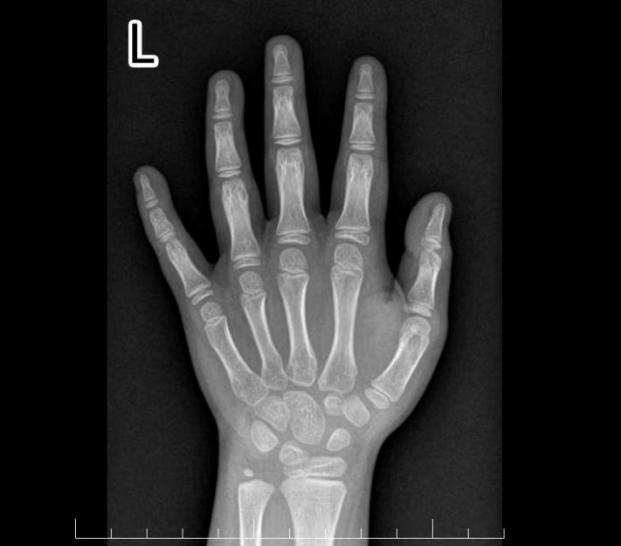

但好在小佳的骨龄结果只有7.7岁,低于实际年龄0.3岁(骨龄与实际年龄相差1岁之内属于正常),骨骺尚未闭合,身高还有生长空间,但预测成年身高只有149.7cm。